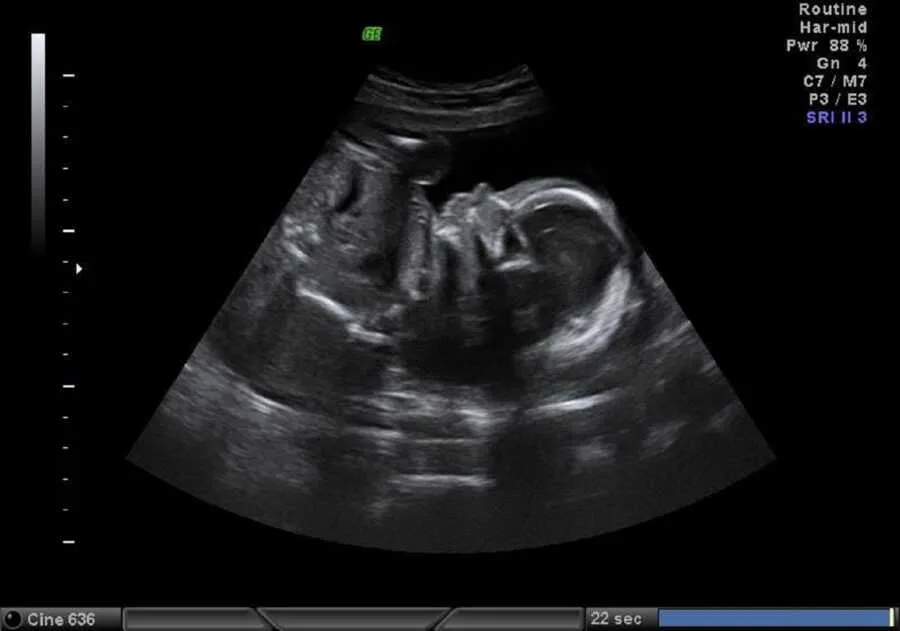

Her doctor did not treat her kindly. He dismissed her concerns, ignored Jordan, and set a due date that never seemed to fit. She knew he was breech when she felt the baby’s head high in her belly. The office insisted she couldn’t say, but an ultrasound proved her right. A C-section was booked for November 9 at eight in the morning. It wasn’t the birth she had imagined but the one ahead of her. On surgery day, the operating room felt cold and bright.

The spinal needle, the staff chatter, the rising panic, then Jordan’s hand in hers. When they lifted their son, Malachi, into the light, he looked like an angel. Moments later, he was taken away for breathing trouble. She lay in recovery, waiting for her baby, who did not come. By the time she could move, she was wheeled past other new mothers with their babies and felt her own arms ache with the absence. That night, she finally saw him in an incubator, tiny and peaceful, and learned he had been born at thirty-six weeks because the dates had been wrong.